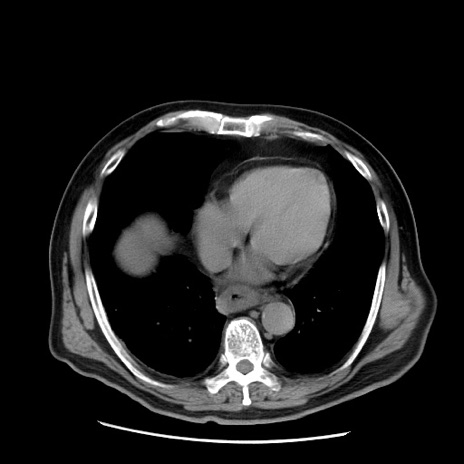

症例20(横断像)

【症例】 60歳代男性

【主訴】 腹部膨満、嘔吐

【現病歴】5日前頃より倦怠感を認め食事量減少し4日前の朝嘔吐、食事摂取困難となった。 3日前近医受診し点滴施行され整腸剤などを処方された。 当日他院を受診し、腹部膨満著明、炎症反応の上昇(CRP10.8、WBC11200)あり、紹介受診となる。

【身体所見】 意識JCS1 受け答えがはっきりしないBP 111/57mHg、 P 67bpm、、BT35.2°C、SpO2 97%(RA)、 腹部:膨隆、打診で鼓音あり、全体的に圧痛有り、腸蠕動音(-)、反跳痛ははっきりせず。

【データ】WBC 11400、CRP 14.20